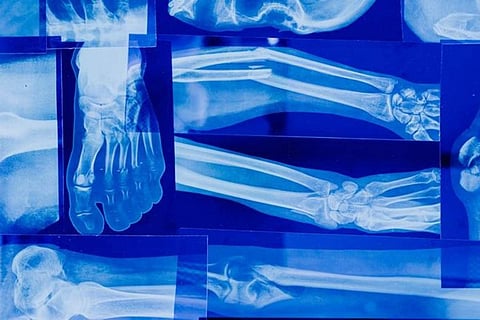

Frequent Fractures:

Among the conspicuous markers of weakened bones are recurrent fractures or breaks, frequently arising from minor accidents or tumbles. Those grappling with diminished bone strength often find fractures to be easily incurred and protracted in their healing. Detecting heightened susceptibility to fractures should prompt a medical evaluation to ascertain the underlying triggers.